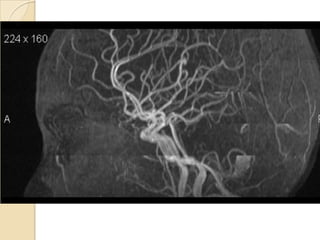

Arteries of the brain (lateral view) - MRA

1. Anterior cerebral artery

2. Anterior communicating artery

3. Basilar artery

4. branches (in insula) of middle cerebral artery

5. Cavernous portion of internal carotid artery

6. Cervical portion of internal carotid artery

7. Genu of middle cerebral artery

8. Intracranial (supraclinoid) internal carotid artery

9. Middle cerebral artery

10. Ophthalmic artery

11. Petrous portion of internal carotid artery

12. Posterior cerebral artery

13. Posterior cerebral artery in ambient cistern

14. posterior cerebral artery in interpeduncular

cistern

15. Posterior communicating artery

16. Posterior inf cerebellar artery.

17. Quadrigeminal portion of posterior cerebral

artery

18. Superior cerebellar artery

19. Vertebral artery